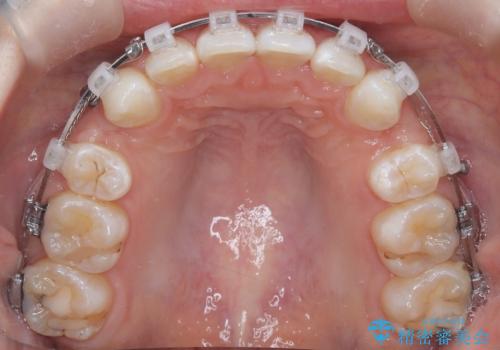

- 右上の八重歯と歯のデコボコ、そして上下の歯の中心(正中)のズレを気にされて来院されました。精密な検査の結果、歯が並ぶスペースが不足しているため、上顎の小臼歯(前から数えて4番目の歯)を抜歯し、そのスペースを利用して歯並び全体を整える治療計画を立案しました。これにより、八重歯の位置を適切に改善し、叢生(歯のデコボコ)を解消するとともに、上下の正中線のズレも改善することを目指します。

今回の矯正治療では、歯が並ぶスペースを確保するため、上顎の小臼歯を抜歯しました。抜歯によってできたスペースを有効活用し、ワイヤーやブラケットを使って右上の八重歯を適切な位置へ移動させ、叢生を解消していきました。また、治療を通じて上下の歯の中心である正中線のズレも改善するよう、慎重に歯を動かしました。治療の結果、長年気にされていた八重歯と歯のデコボコが解消され、上下の正中線も一致。機能的にも審美的にもバランスの取れた、美しい歯並びと笑顔を獲得していただけました。